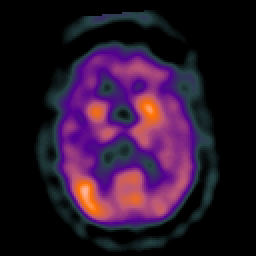

Subacute Stroke overlay -- Slice #13

[Home][Help][Clinical] Slice 13